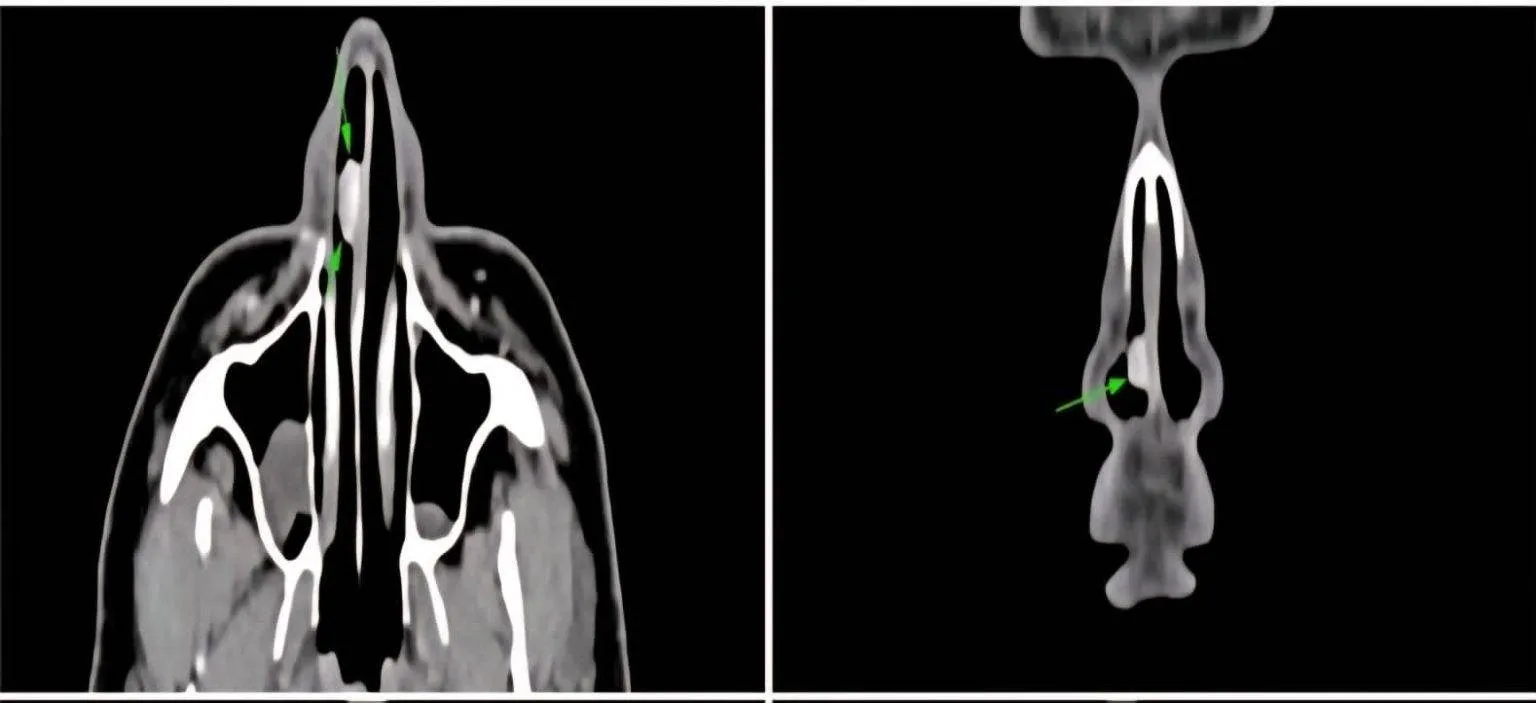

નાકમાં આવી ગાંઠ અતિ દુર્લભ, દર્દીને સતત રક્તસ્ત્રાવની તકલીફ

સામાન્ય રીતે આ પ્રકારનું હેમેન્જિયોમા કિડની અથવા યુરિનરી સિસ્ટમમાં જોવા મળે છે, પરંતુ નાકના પડદામાં તેનો વિકાસ થવો અત્યંત વિરલ છે. દર્દીને છેલ્લા બે મહિનાથી એક બાજુ નાકમાંથી રક્તસ્ત્રાવ થતો હતો, સાથે નાક બંધ રહેવું અને માથાનો દુખાવો પણ અનુભવાતો હતો. એન્ડોસ્કોપિક તપાસ દરમિયાન જમણા ભાગમાં લાલ, મસા જેવી અસામાન્ય રચના દેખાતા ડૉક્ટરે વધુ તપાસ માટે કોન્ટ્રાસ્ટ CT સ્કેન કરાવ્યું, જેમાં ખુલ્યું કે ગાંઠ રક્તવાહિનીઓની ગૂંચથી બનેલી છે.

આયોજનપૂર્વકની એન્ડોસ્કોપિક સર્જરી, ટ્યુમર સંપૂર્ણપણે દૂર

આ દુર્લભ સ્થાને સર્જરી કરવી પડકારજનક હોવાથી ડૉ. ઠક્કરે અનુભવી તકનીક સાથે વિશેષ તૈયારી કરી. સર્જરી દરમિયાન ઓછું બ્લીડિંગ થાય તે માટે યોગ્ય સાધનો અને આધુનિક એન્ડોસ્કોપિક પદ્ધતિનો ઉપયોગ કરવામાં આવ્યો. સમગ્ર ટ્યુમરને સફળતાપૂર્વક દૂર કર્યા બાદ કરવામાં આવેલી બાયોપ્સીમાં પુષ્ટિ થઈ કે લીઝન Anastomosing Hemangioma જ હતું, જે કેન્સરજન્ય નથી પરંતુ તેની દુર્લભતા તેને વૈજ્ઞાનિક રીતે વિશેષ બનાવે છે. દર્દીની હાલત સર્જરી બાદ સંપૂર્ણપણે સામાન્ય છે અને શ્વાસ લેવામાં પણ કોઈ તકલીફ રહી નથી.